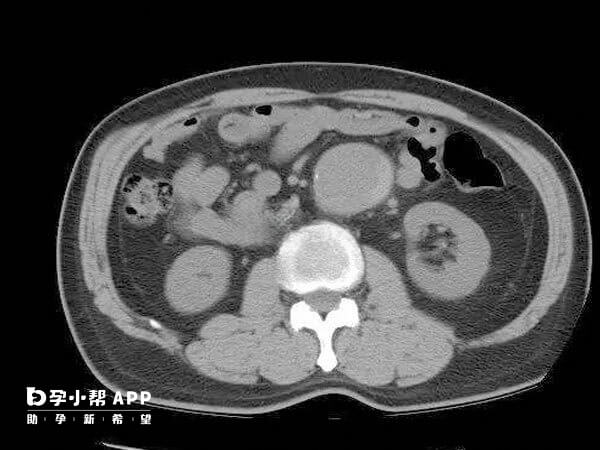

4、利用腹腔镜探查盆腔以了解子宫大小形态和位置与周围脏器关系。